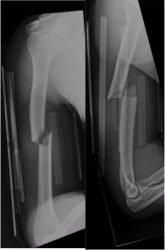

Humeral shaft fracture